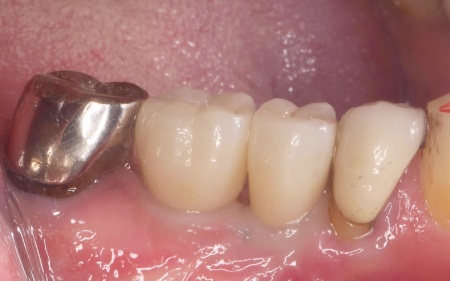

| 行ったご提案・治療内容 | 診断結果を丁寧に説明したうえで、右下奥歯2本の抜歯を提案したところ同意いただきました。 併せて抜歯後に歯を補う方法として、以下2つの選択肢をお伝えしました。 ①前後の歯を削って橋のようにつなげた被せ物で歯を補うブリッジ治療 ②あごの骨に人工の歯根を埋め込み、その上に人工歯を取り付けるインプラント治療 それぞれの特徴や注意点について説明したところ、患者様は②のインプラント治療を希望されました。 まず右下奥歯2本の抜歯を行い、その後、約3ヶ月間歯ぐきや骨が十分に回復するのを待ちました。 |

治療後